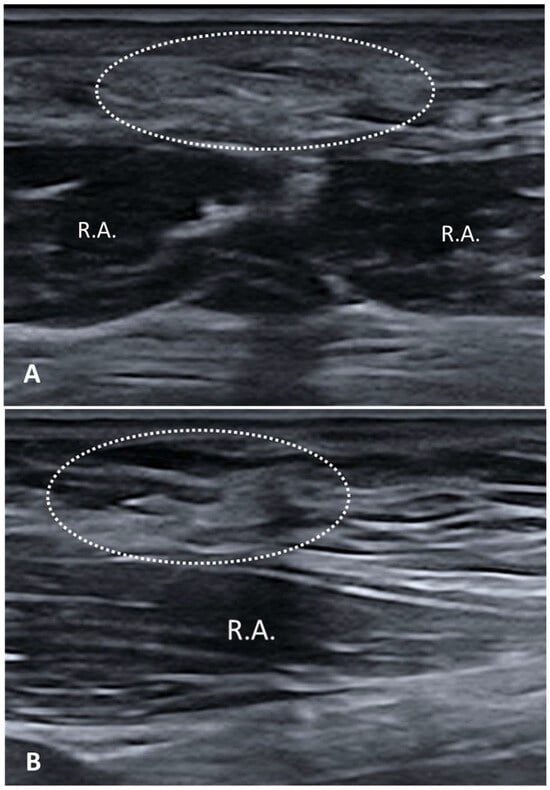

3.1. Normal Ultrasonographic Appearance of Fasciae

- Fan, C.; Guidolin, D.; Ragazzo, S.; Fede, C.; Pirri, C.; Gaudreault, N.; Porzionato, A.; Macchi, V.; De Caro, R.; Stecco, C. Effects of Cesarean Section and Vaginal Delivery on Abdominal Muscles and Fasciae. Medicina 2020, 56, 260. [Google Scholar] [CrossRef] [PubMed] [PubMed Central]